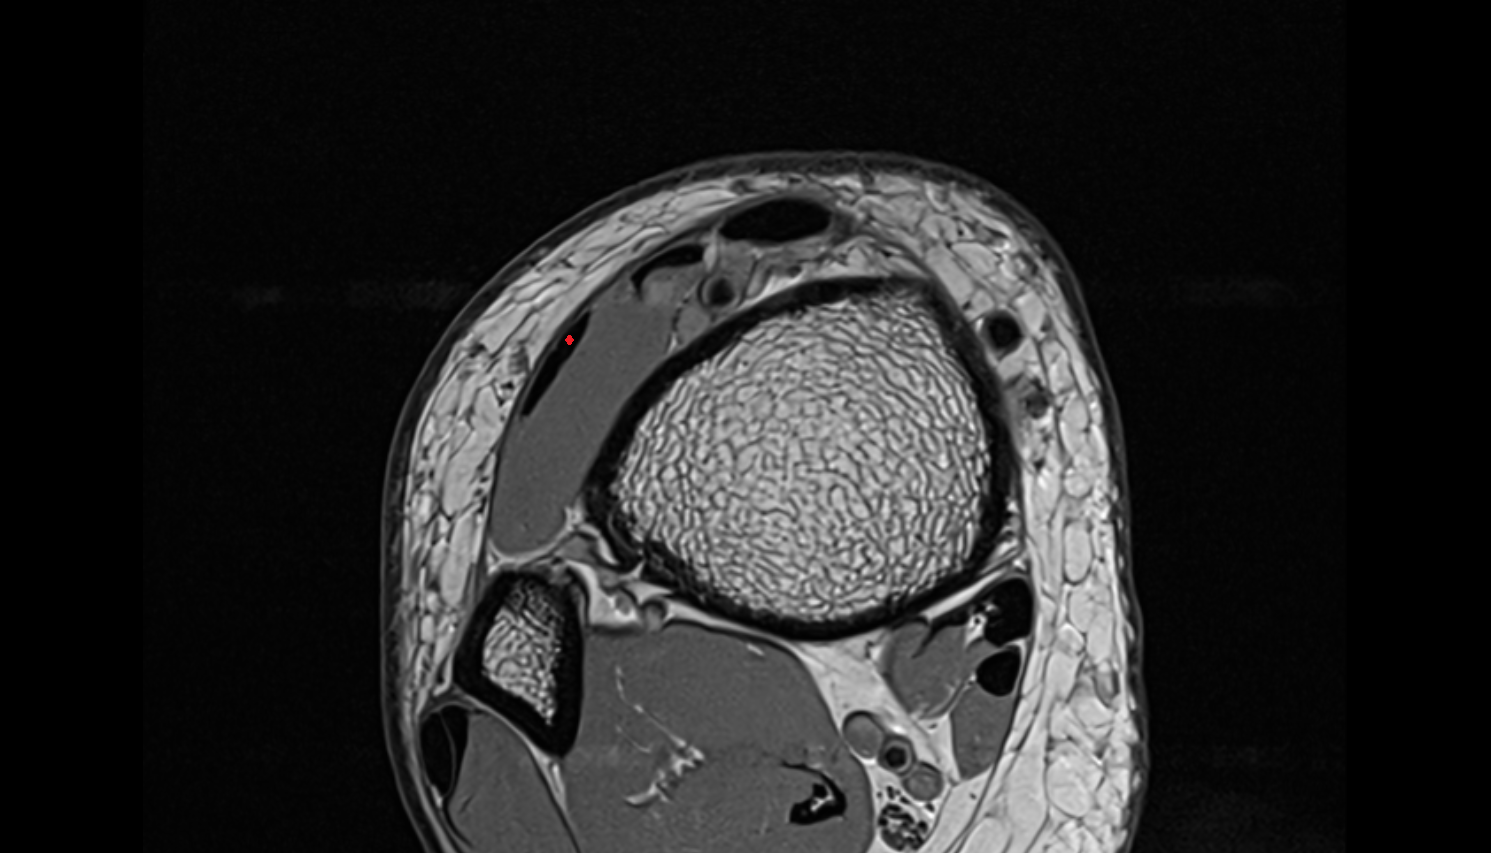

- Temporomandibular joint

- Mandibular condyle

- Mandibular fossa

- Articular disc of temporomandibular joint

- Articular eminence